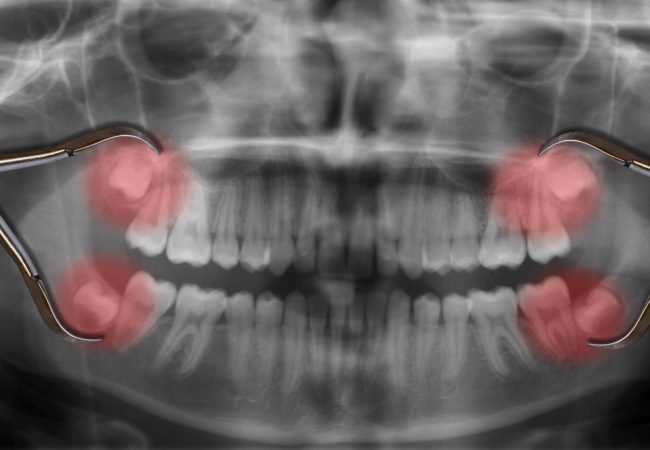

Wisdom teeth are vestigial molars that human ancestors used to grind down plant tissue. The skulls of human ancestors had larger jaws with more teeth & as human diets changed, smaller jaws were naturally selected, yet the 3rd molars still commonly develop http://ow.ly/nMae30oikb5